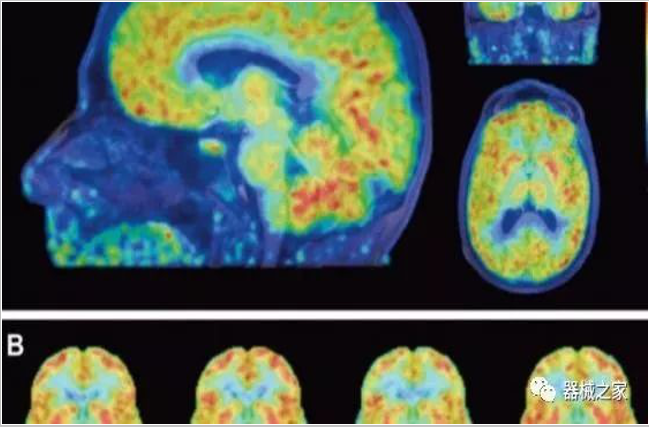

PET掃描顯示成年女性大腦比男性年輕三歲!

大開眼界~